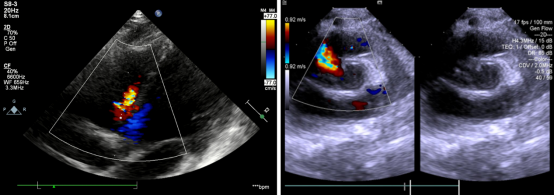

图1:患者封堵前心脏彩超检查显示室间隔缺损